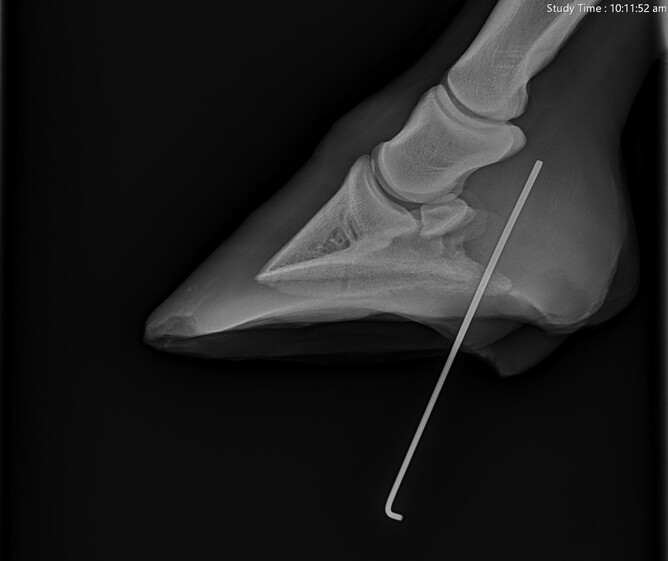

The initial reaction to seeing a nail or other object in the foot is most likely to want to pull it out. This is not always the most helpful approach however in terms of figuring out which structures have been compromised. It can be useful to x-ray the foot and the limb with the object still in place. This enables us to see exactly where the object has been and which structures we need to evaluate further. This is particularly useful if the object has penetrated through the frog, as the elastic tissue in this area can often make it difficult to find the tract again once the object is removed.

Solar punctures should always be treated as potential emergencies - we are particularly concerned about penetrating injuries to this area as the foot and lower limb contain many sensitive and vital structures. Damage or infection in these areas can cause career-ending lameness or can even be life threatening. Within the foot, we can appreciate (Figure 1):

- The coffin bone and the navicular bone

- The deep digital flexor tendon and impar ligament

- The coffin joint

- The navicular bursa and digital tendon sheath (sheaths encasing the tendons and allowing them to glide smoothly over bone and around corners)

- The digital cushion

These structures lie very close to the ground - there is only on average 3cm from the sole of the foot to the navicular bone in the average sized horse.